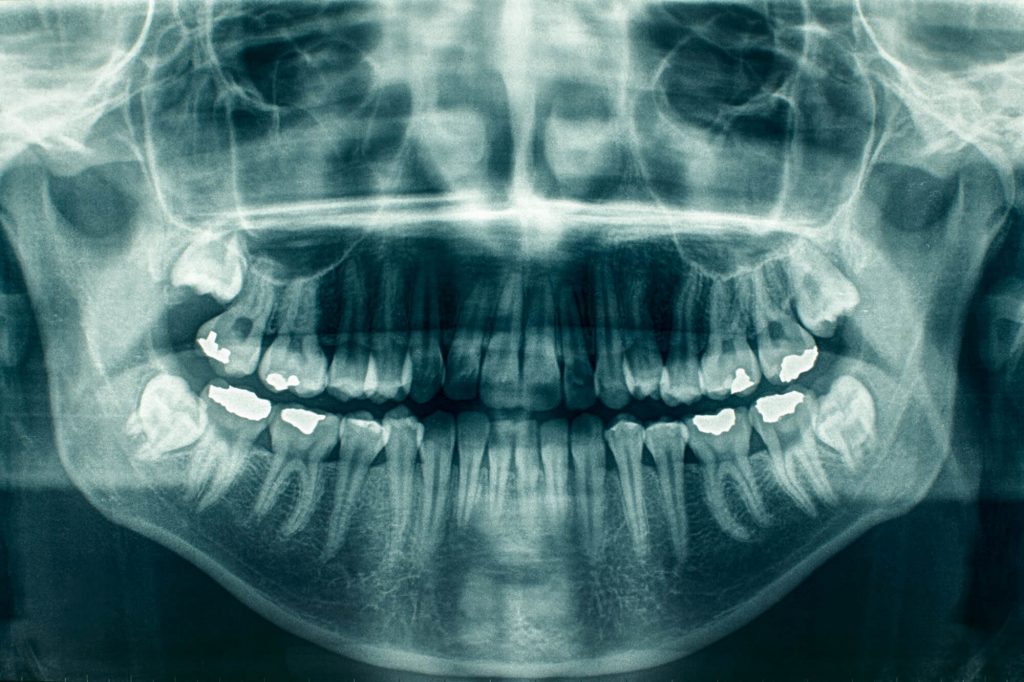

Panoramic ("pan") x-rays produce a wrap-around radiographic image of the patient's mouth that measures 15 cm x 30 cm (5" x 11"). This is important for examining the patient's jaw and the relationship between the teeth. A panoramic machine can photograph numerous areas of the patient's anatomy. In dental practice, the pan normally has its own small alcove. Many offices, on the other hand, have specialized x-ray rooms where the machine is kept.